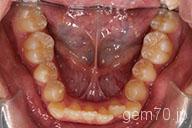

症状:叢生装置:セラミックブラケット | 非抜歯(歯を抜かない)世代:中学生

主訴)歯のでこぼこ

診断)叢生

年齢)14歳

使用装置)マルチブラケット装置

治療方法)非抜歯(歯を抜かない)

治療期間) 2年4ヵ月 通院回数 27回